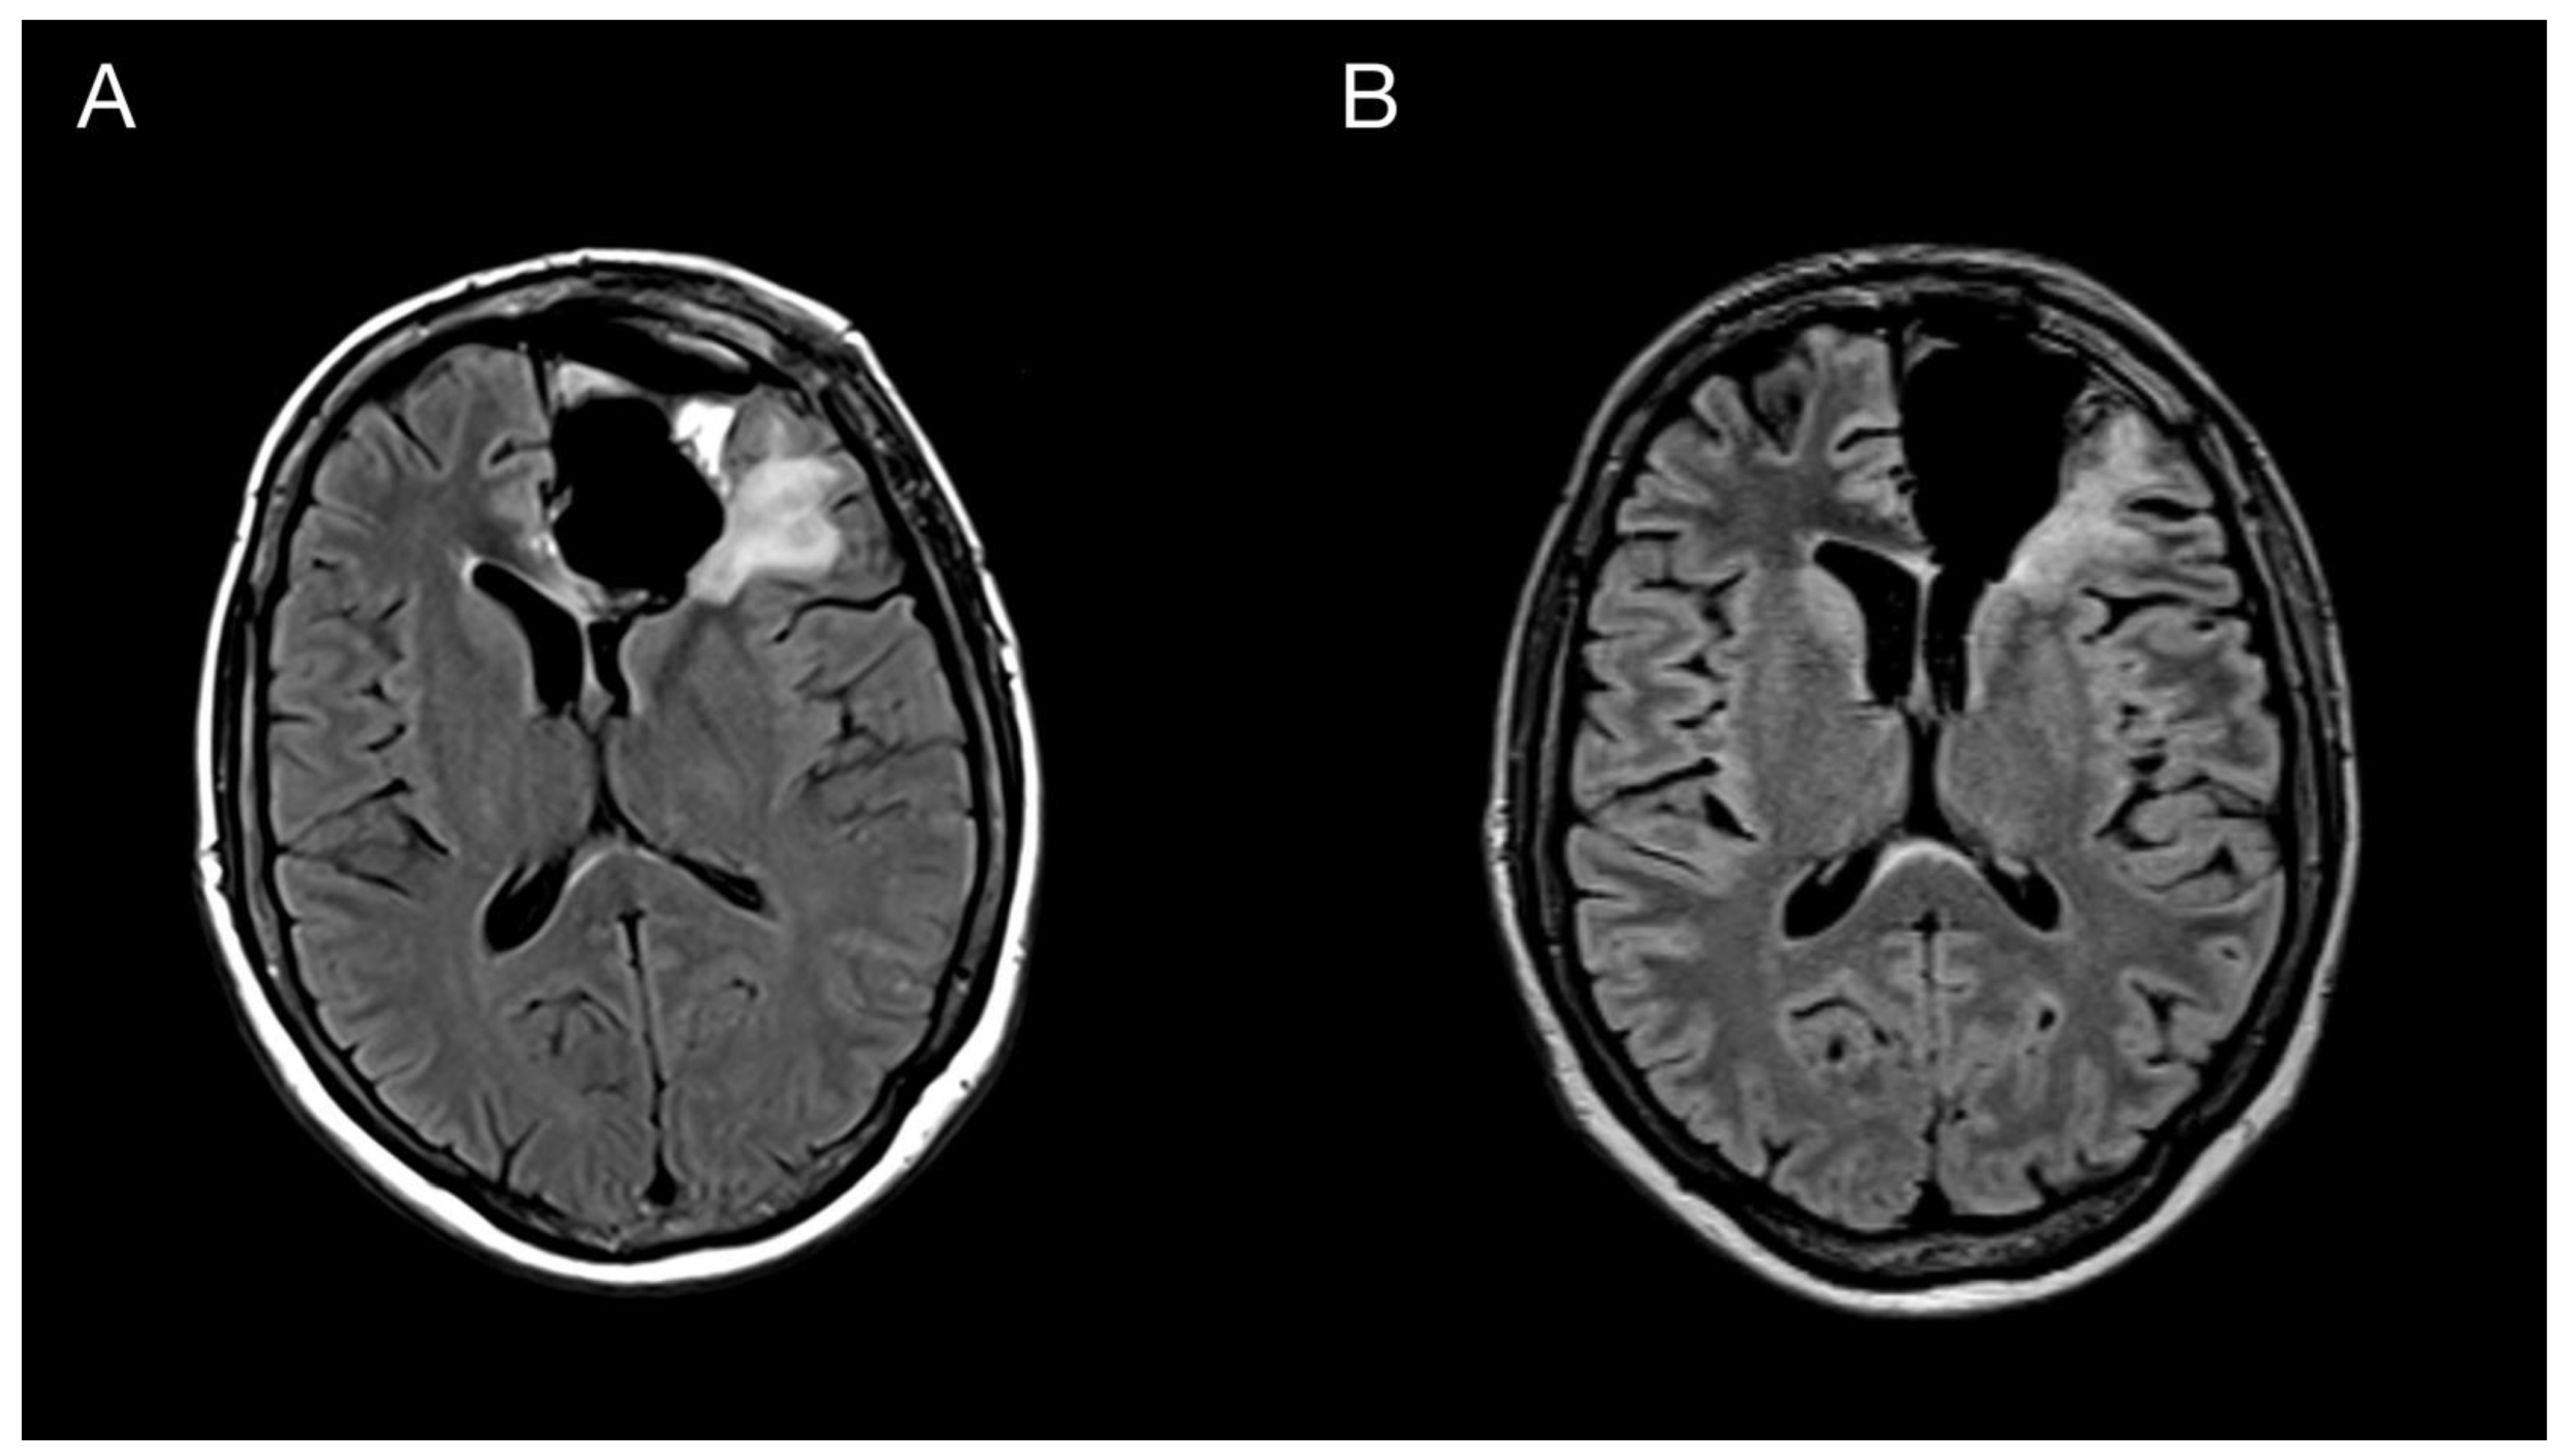

2. Case Report